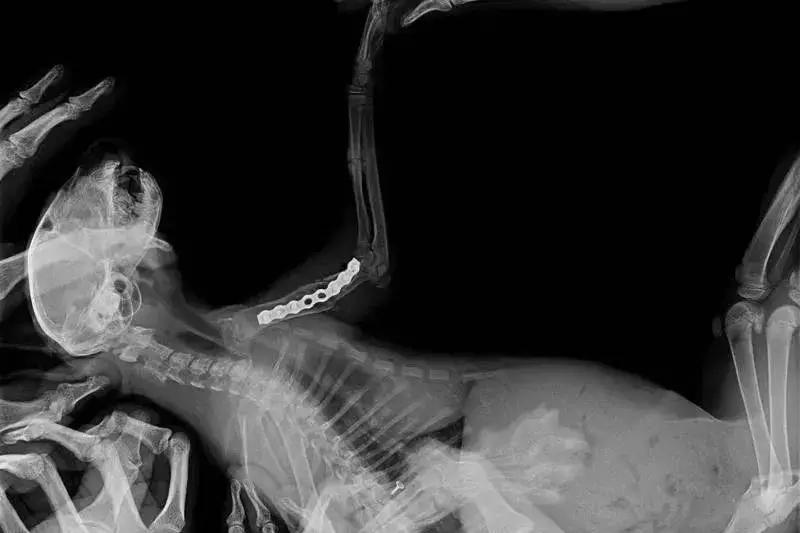

术前x-ray显示,六一的骨折为 左前肢肱骨中远段骨折 ,骨折类型为横骨折。

术后X线片

六一小朋友的年龄仅有3个月,体重仅1kg,对于这样的幼猫,陈旧性骨折发生二次骨折的内固定手术无疑是一个严峻的挑战。六一的主治医生张海峰院长使用接骨板板对六一进行了骨折的内固定。